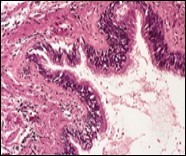

Figure 2.Ciliated cutaneous cyst with an undulating layer of ciliated cuboidal epithelium and supporting fibrous tissue framework (12).

Cystic structures cogitated within deep dermal or subcutaneous tissue can be impacted with haemorrhagic fluid. Cyst lining is smooth, regular and is essentially composed of a singular layer of columnar epithelium with focally pseudostratified columnar epithelium, a circumscription of loosely configured, well vascularized, fibroconnective or fibrocollagenous tissue and an absence of inflammatory infiltrate.

Cutaneous ciliated cyst is layered with a singular layer of ciliated epithelial cells which are chiefly constituted by cuboidal to columnar epithelium, traversed by partially configured fibrous tissue septa with an admixture of randomly dispersed, intraluminal papillary projections akin to those cogitated in the fallopian tube. Superimposed epithelium is inundated with well vascularized, parallel bundles of collagen although smooth muscle is absent 7, 8.